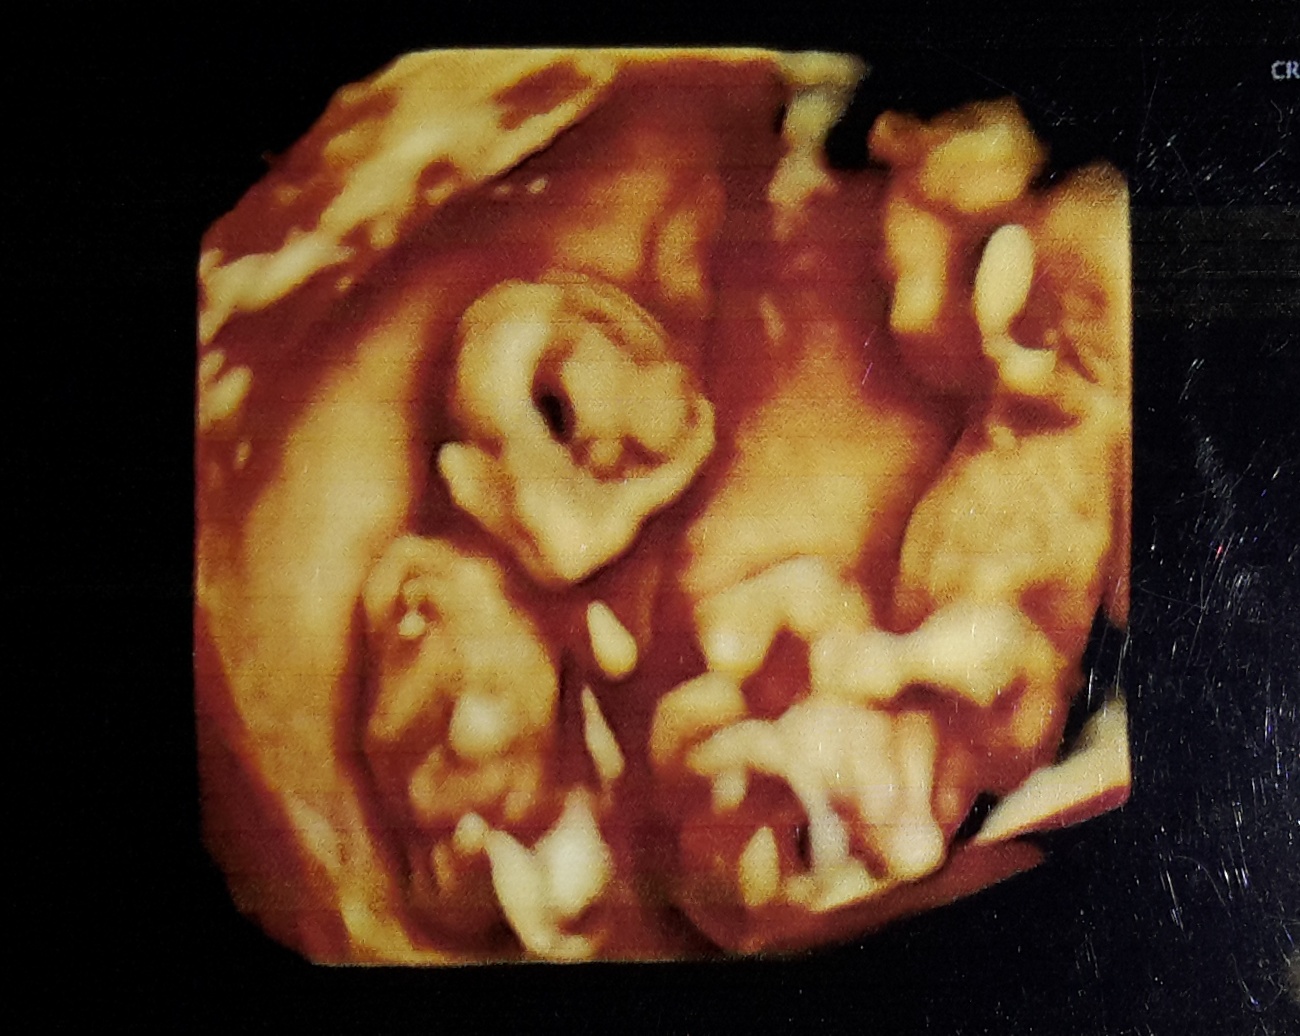

I just got my 19 weeks ultrasound. I am having fraternal (non identical) twins.

Any guesses please?